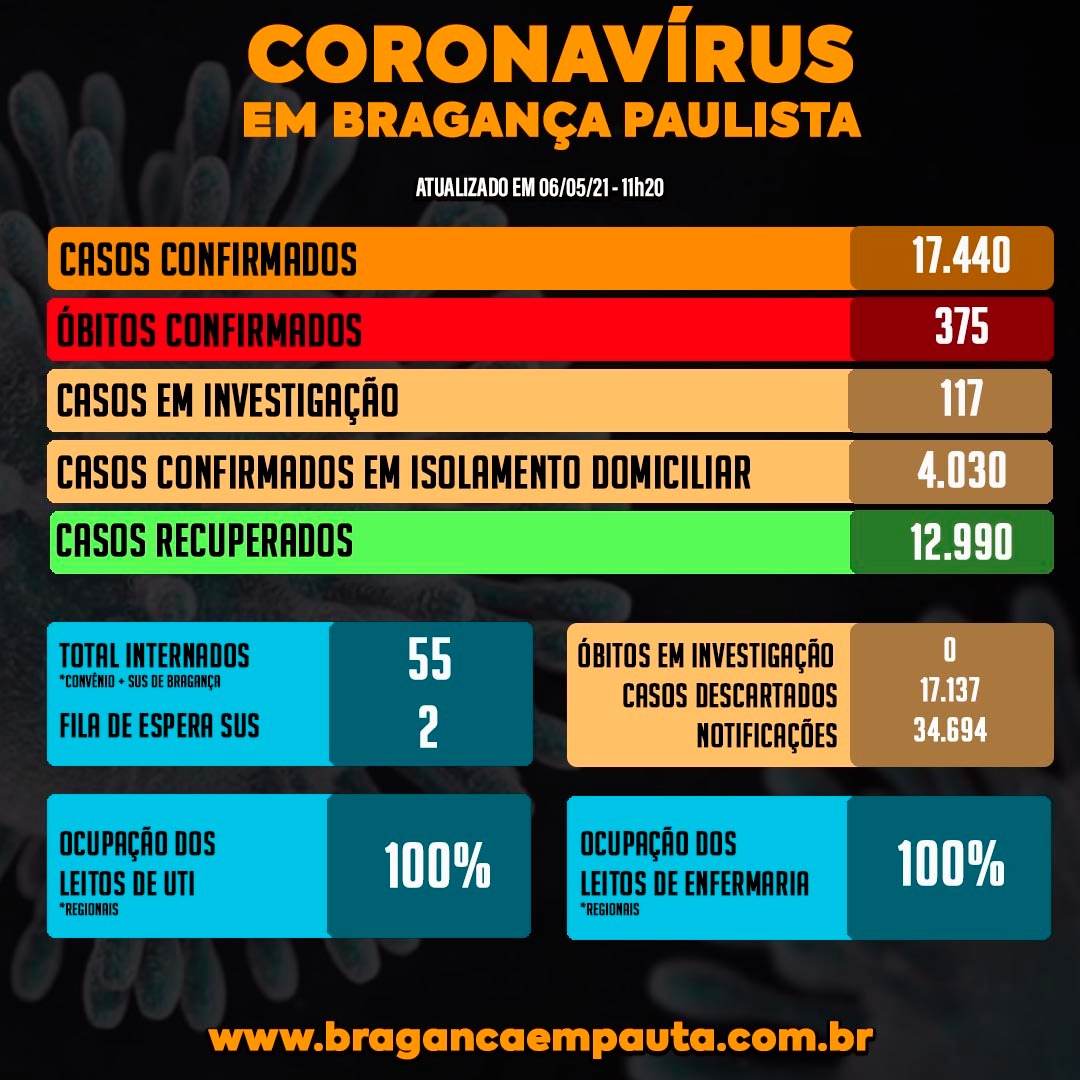

Bragança volta a ter 100% de ocupação de UTI e fila de espera por vagas

Embora os números dos últimos dias da COVID-19, em Bragança Paulista, mostrassem sinais de queda e desaceleração, nas últimas 24 horas, eles voltaram a subir. A taxa de ocupação dos 46 leitos de UTIs regionais, que ontem pela primeira vez em 64 dias havia baixado, voltou a subir indo de 93% para 100%.

Já a taxa de enfermaria do Hospital de Campanha instalado na Santa Casa foi de 76% para 100% em 24 horas. Além disso, vale lembrar que dos 20 leitos de enfermaria da Vila Davi 1 deles está ocupado.

O boletim indica ainda que há um paciente na fila de espera por vaga de leito de UTI e um por vaga de enfermaria. Geralmente, nestes casos, o paciente fica na UPA Vila Davi, aguardando a transferência via Central de Regulação de Ofertas de Serviços de Saúde (CROSS).

Bragança Paulista tem, agora, 375 mortes confirmadas em decorrência da COVID-19 desde o início da pandemia. Destas, 103 mortes aconteceram entre março e dezembro de 2020. Outras 272 de janeiro deste ano até agora.

Em janeiro, aliás, foram 25 mortes, em fevereiro 34. Após a revisão março tem 126 mortes e abril 78 mortes. Maio já tem 9 mortes confirmadas até aqui.

Os 46 leitos regionais de UTI e os 30 de enfermaria voltaram a ter 100% de ocupação. Um, dos 20 leitos de enfermaria da UPA Vila Davi está ocupado.

Há um paciente na fila do CROSS por leito de UTI e 1 de enfermaria.

De acordo com boletim, aliás, o número total de internados subiu nas últimas 24 horas de 49 para 55. Dos, 55 moradores de Bragança Paulista internados, 45 já tem confirmação de COVID-19 e 10 pacientes aguardam os resultados de exames.

- 17.440 casos confirmados desde o início da pandemia

- 12.990 pacientes recuperados, sendo 208 nas últimas 24 horas

- 4.030 pacientes positivos em isolamento domiciliar

- 375 mortes confirmadas